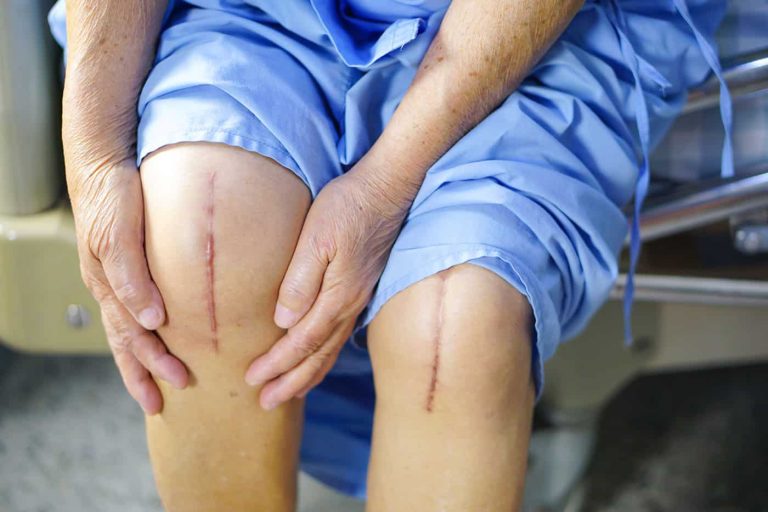

4. Koje su moguće tegobe nakon artroplastike kolena?

Nakon operacije kolena mogu se javiti

• bol, otok i ukočenost kolena

• otežano kretanje